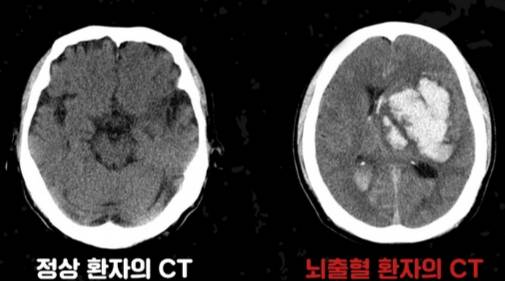

뇌에 갑작스럽게 타격이 가해지는 질환이 뇌졸중이다. 뇌졸중은 △뇌혈관이 막히는 '뇌경색' △혈관이 터지는 '뇌출혈'(출혈성 뇌졸중)로 나뉜다. 이 가운데 뇌출혈은 전체 뇌졸중의 약 20%를 차지한다.

뇌출혈이 발생한 순간부터는 뇌 손상이 빠르게 진행한다. 그 이후엔 뇌부종과 재출혈로 악화할 수 있다. 이런 증상이 있으면 최대한 빨리 병원으로 와야 한다. 뇌졸중 가운데 뇌경색은 막힌 혈관을 개통시킬 수 있는 골든타임이 있으나, 뇌출혈은 골든타임이 없다. 즉, 아무리 병원에 빨리 오더라도 회복이 불가능한 경우가 많지만, 최대한 빠르게 응급실로 가는 것이 최소한의 장애를 위한 유일한 방법이다.